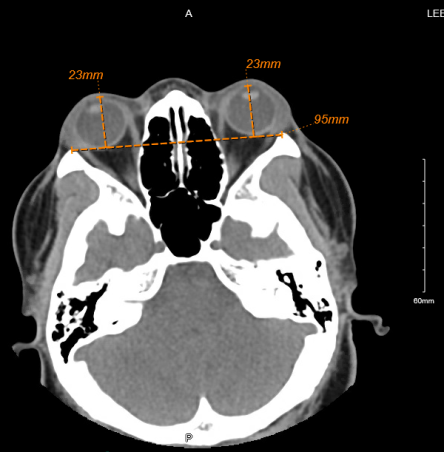

Radiologic Exophthalmometry

Radiologic exophthalmometry utilizes computed tomography (CT) to provide an objective measurement of proptosis. Multiple techniques exist for measuring proptosis with CT. In one method, a horizontal line is drawn between the lateral orbital rims that bisects the lens in the axial plane. A perpendicular line is then drawn to the apex of the cornea and measured.

In another method, a line is drawn between the lateral and medial orbital rims on each side that bisects the lens in the axial plane. A perpendicular line is then drawn to the apex of the cornea and measured.